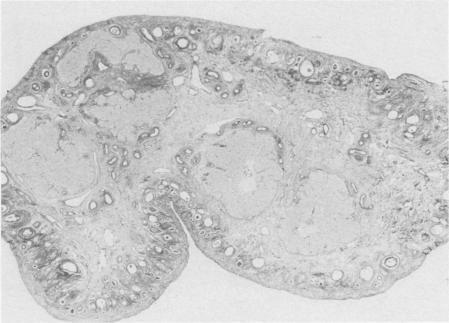

Ninety-eight reproductive tracts from dogs at different postpartum time periods were used to investigate stages of normal involution. Seventy-eight reproductive tracts were obtained from the field, and 20 obtained surgically for gross and microscopic examination. Plasma progesterone was measured in 22 dogs at various times postpartum. The uterine horns during the first week postpartum were dilated and edematous. The placental sites were 1.5-3 cm in width, rough, granular and covered with mucus and a few blood clots. By the fourth week the placental sites were thick, grayish-tan and nodular with a few blood clots within nodules. The uterine horns during the seventh week were greatly contracted and the placental sites were narrow and light in color. A few nodules were still present on the surface. By the ninth week the uterine horns were uniform in shape and contracted with a narrow lumen. The placental sites appeared as a narrow brown band. Histologically the placental sites during the first week postpartum were covered by an eosinophilic staining necrotic mass and a few intact epithelial cells scattered on the surface as an interrupted single layer. Under the necrotic mass, large eosinophilic staining cells in moderate number were scattered throughout the lamina propria of the placental site. These cells were considered to be decidual cells. By the fourth week the placental sites were covered by a large lobulated mass of collagen fibers. The uterine glands were greatly dilated and degenerate, and mononuclear cell infiltration in the lamina propria was pronounced. By the seventh week, large masses of collagen fibers were detached from the surface, and endometrial glands were normal in size and shape. By the ninth week surface sloughing was completed. However, regeneration and replacement of the endometrial lining from the mouth of the uterine glands continued until the end of the twelfth week when the involution process was completed. The progesterone levels were very low for eight weeks postpartum.

98条处于不同产后时期的犬生殖道用于研究正常 involution 的阶段。78条生殖道取自野外,20条通过手术获取用于大体和显微镜检查。在产后不同时间对22只犬测量血浆孕酮。产后第一周子宫角扩张且水肿。胎盘部位宽1.5 - 3厘米,粗糙、呈颗粒状,覆盖有黏液和少量血凝块。到第四周时,胎盘部位增厚,呈灰棕色且有结节,结节内有少量血凝块。第七周时子宫角大幅收缩,胎盘部位变窄且颜色变浅。表面仍有一些结节。到第九周时,子宫角形状均匀且收缩,管腔狭窄。胎盘部位呈现为一条狭窄的棕色带。组织学上,产后第一周的胎盘部位被嗜酸性染色的坏死物质覆盖,表面有一些完整的上皮细胞散在分布,形成间断的单层。在坏死物质下方,中等数量的大嗜酸性染色细胞散在分布于胎盘部位的固有层。这些细胞被认为是蜕膜细胞。到第四周时,胎盘部位被大量分叶状的胶原纤维团覆盖。子宫腺大幅扩张并退化,固有层单核细胞浸润明显。到第七周时,大量胶原纤维从表面脱落,子宫内膜腺大小和形状正常。到第九周时表面脱落完成。然而,从子宫腺开口处开始的子宫内膜衬里的再生和替代持续到第十二周结束时 involution 过程完成。产后八周孕酮水平非常低。